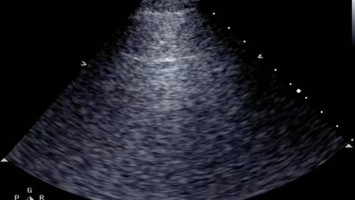

Diese entscheidende Frage stellt sich im Fall einer 93-jährigen Patientin mit starker Dyspnoe, Thoraxschmerzen und Hypotonie. Das Aufnahme-EKG zeigt eindeutig einen ST-Hebungsinfarkt, der Verdacht auf ein kardiales Lungenödem steht im Raum. Der lungensonografische Befund jedoch passt nicht dazu.

Bildnachweise